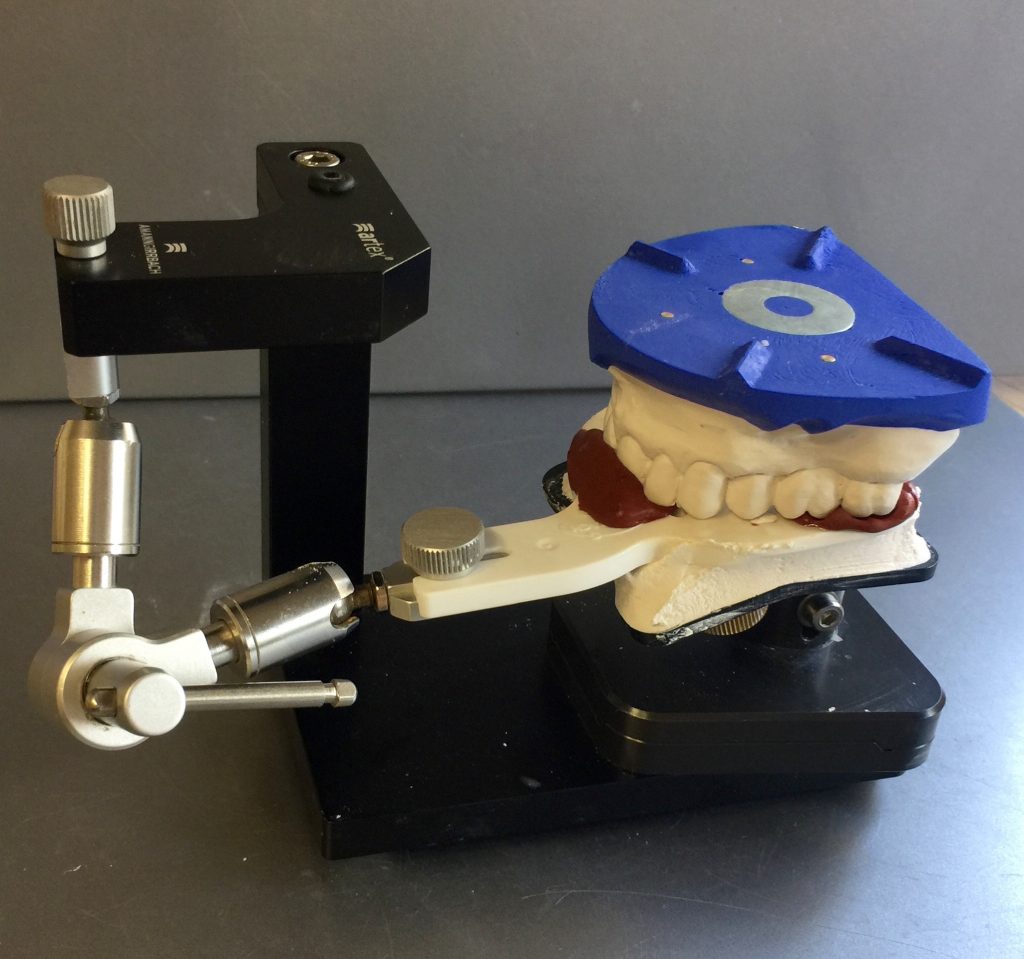

Autores: PRÓLOGO Asimismo, desde el punto de vista pedagógico, el profesional nobel en la materia tiene a su alcance la posibilidad de corregir cualquier posición implantaría en el ordenador, planear los provisionales y plasmarlos en la bio réplica antes de tocar al paciente a operar. Todos estos razonamientos nos llevan a presentar un caso de condiciones muy favorables para poner en práctica estos métodos como primer acercamiento a una Odontología Digital de alta calidad, con medios informáticos, que ya están presentes en la profesión de hoy en día, y será la protagonista única del futuro. Por otro lado, después de numerosos estudios que nos llevan a plantear el “gap” entre implante y pilar(abuttment), como principal responsable de la periimplantitis dado que la microbiota presente en el mismo es imposible de limpiar y en su presencia la cortical ósea reacciona reabsorbiéndose, nos ha llevado a utilizar implantes monobloc ya que los ejes implantarios y protéticos coincidían, y nos permitían su uso. Además, el circonio, ha mostrado a la luz de estudios muy recientes, una preservación y adhesión de los tejidos blandos superiores al titanio, tanto en su tratamiento de superficie de la rosca como a nivel gingival. DESARROLLO Paciente varón de 68 años, con antecedentes de radio/quimioterapia cinco años antes, con Rehabilitación Oral de los cuatro cuadrantes, con una Oclusión Mutuamente Compartida conservada, (REF.8) la que fracasa en el cuadrante 4, 19 años después. El mismo presentaba un puente de porcelana sobre circonio con pilares en 44 y 47, reemplazando el edentulismo de 45 y 46. Se produce la fractura del PM del 44, y ante una endodoncia antigua y corta, se decide implantar las zonas edéntulas, conservando temporariamente los pilares, hasta producida la oseointegración, para entonces también exodonciar el 44. DIAGNÓSTICO Tomamos impresiones del maxilar antagonista, Arco Facial Estático y realizamos montaje del mismo mediante la sistemática ARTEX. Producimos la relajación del músculo Pterigoideo Externo, para obtener la ORC (Oclusión en Relación Céntrica) mediante el método de Laminillas de Long, basado en el concepto de INERVACIÓN RECÍPROCA. Esto nos permitirá montar el maxilar inferior, tanto en su forma de: La primera para practicar la cirugía guiada y comprobar su eficacia, y el modelo de yeso para ser escaneado y confeccionar la GUÍA QUIRÚRGICA. La Biorréplica la obtenemos transformando los archivos DICOM que nos da el CBCT en archivos STL, y a partir de ellos, mediante una tecnología de PROTOTIPADO RÁPIDO, la obtención de un objeto físico en 3D a través de la aglutinación selectiva de una sucesión de capas de polvo. Procedemos a montar la biorrèplica y el modelo de yeso del caso. Podemos verificar la exactitud de las medidas del hueso residual en la bio réplica y compararlas con el scanner. Arrojando un resultado de 8,5 mm de cortical externa a cortical externa. Pudiendo también medir la distancia hasta el dentario. y comparar gracias a la ventana lateral de la biorréplica Dándonos 22mm de distancia. Con lo cual deducimos que implantes de 4,1mm por 12 mm serán perfectamente rodeados de hueso. Medimos también la distancia desde oclusal del antagonista, hasta el hueso desnudo. Lo mismo que, mediante la utilización de la guía radiológica, con un material radiolúcido colocado en gingival de la misma, podemos medir la altura de la encía. Con lo cual podemos calcular la altura del pilar. Es entonces cuando con el programa COC Diagnostix se realiza la programación final: Obteniendo no solo la ubicación, largo, ancho y ángulo de los implantes sino también los provisionales mediante CAD CAM. Ya entonces podemos hacer la práctica quirúrgica en la bio réplica, mediante la guía quirúrgica, instalando los implantes de prueba que no serán los de circonio, ya que la casa no cuenta con ellos, pero si otros de las mismas dimensiones. TRATAMIENTO Entramos ya en la cirugía propiamente dicha. Antisepsia de la zona a operar y zonas anexas. Comprobación del perfecto ajuste e inmovilidad de la G.Q. en boca durante la cirugía. Marcado de la encía y perforación de la cortical. Visión a través de la Guía de la mínima intervención anterior. Comprobación sin Guía. Incisión mínima mesio distal, para apartar y conservar encía queratinizada. Secuencia de drills, perforando a profundidad requerida Observación del Mínimo Trauma Implantes Strauman de Zirconio Monoblock en blíster y montádo en contrángulo reductor. Instalación controlando torque con contrángulo reductor. Comprobación clínica. Comprobación Radiográfica y con Guía. Toma de impresiones, y armado de modelos con técnicas de pasividad protética. Montaje. Resultado de las provisionales ejecutadas por CAD CAM Al no estar conformes con el resultado decidimos desechar dichas provisorias y optar por repetirlas. Nuevas provisorias realizadas mediante encerado convencional. Estado de los tejidos blandos. Provisorias en boca. Oclusión de Estímulo Inmediato. Ref.10: Carga inmediata .Alberto y Diego Bechelli. Comprobación mediante CBCT post operatorio Componentes del equipo (En la próxima presentación, mostraremos las coronas definitivas de porcelana sobre circonio, y la desoclusión provocada por una OCLUSIÓN MUTUAMENTE COMPARTIDA, sobre estos implantes y otros seis mas) REFERENCIAS

A-BIORRÉPLICA

como

B-MODELO DE YESO

en una posición fisiológica (Oclusión en Relación Céntrica).

REF.8

FIG: 14-15-16-17-18-19-20

Fig. 14

Fig. 15

Fig. 16

Fig. 17

Fig. 18

Fig. 19

Fig. 20